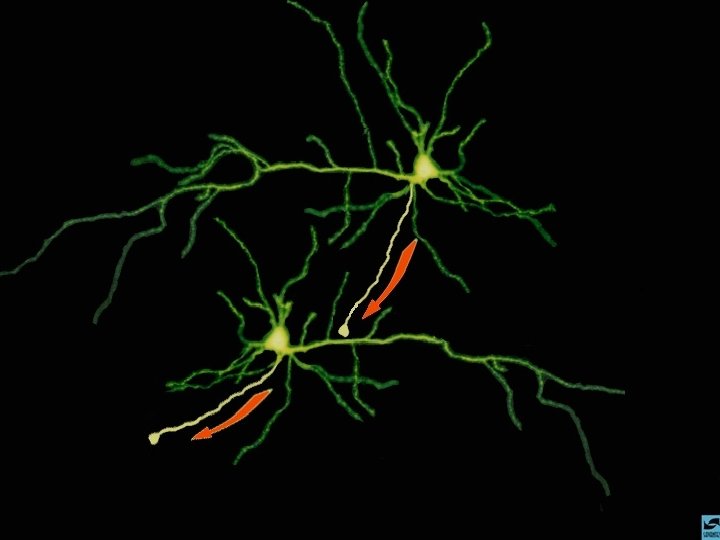

A AÇÃO DAS DROGAS NO SISTEMA NERVOSO CENTRAL O NEURÔNIO Axônio (pré-sinapse) Dendritos (pós-sinapse)

A AÇÃO DAS DROGAS NO SISTEMA NERVOSO CENTRAL A COMUNICAÇÃO ENTRE OS NEURÔNIOS

A AÇÃO DAS DROGAS NO SISTEMA NERVOSO CENTRAL A SINAPSE